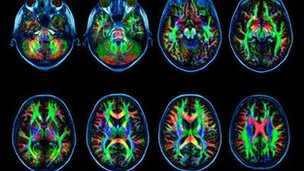

La adicción a internet cambia el cerebro